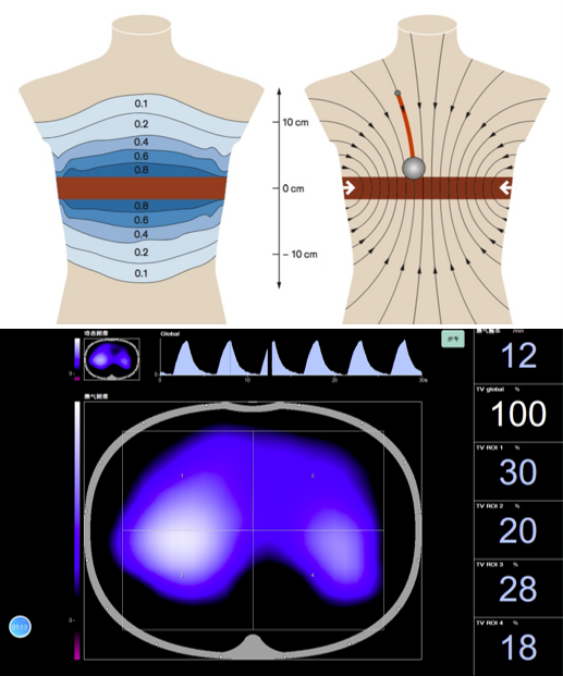

肺部的电阻抗成像是通过16个电极测量局部胸部皮肤的电流,这16个电极首先发射一对已知的交流电信号,然后通过其他电极来测量电流的大小,根据欧姆定律,就可以计算其电阻抗值。如果我们将人体想象成一个导体,在吸气运动时,胸廓向外向上拉伸,此时可以将其看作一个导体被拉长,体积不变,横截面积变小,那么电阻实际上是增加的。根据这一特点,我们通过测量电流大小,进而计算其电阻大小,且电阻大小与体内含气值呈正相关,通过测算就能够将其转化成为体内含气量,建立气体变化值与对应的人体电阻抗值的对应关系。在一对电流发射完之后,它可以很快转换到其他电极上继续进行测量。通过不同角度的测量,最终形成类似于CT影像的图像,但其清晰度较CT低很多,分辨率约为CT图像的1/256。通过340个网格形成了208个由不同电压形成的图像,去掉滤波后最终形成了我们看到的横截面图像,然后再与其测量过的几百例患者建立的模型进行图像重建,最终得到电阻抗图像。

在机械通气参数设置时,不仅要符合病理生理的改变,还要符合患者个体化特点。以ARDS为例,典型的ARDS会出现肺顺应性下降,但通过CT影像发现这种肺顺应性的下降并非均匀、一致的,而是分层的,例如在腹侧区域,可能表现为过度膨胀;在腹侧下一区域,可能是正常通气;在靠近背侧区域,可能是周期性开放,而在背侧区域,实际上是处于肺不张状态。这种形态学变化提示我们,典型ARDS肺顺应性下降的变化实际上是病变与通气的不均一。

在机械通气时,我们测量的静态肺顺应性实际上是将肺看作为一个整体,无论如何调整呼吸机参数,仍无法知道其内部的具体变化。而对于局部肺顺应性,通过EIT的监测能够看到以电极束带为核心整个肺的20%~30%的区域中动态图形的变化,同时,它能够最大限度地将肺还原形态学的特点。因此,无论是分层还是区分象限,实际上都遵循了肺形态学的特点和不同疾病通气的特点。所以,EIT的优势在于其不仅能将肺看成一个整体,而且能考虑中间的不同变化。